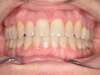

Cas 4 : Description

Chevauchement sévère. Traitement multibague sans extraction.

Avant

Après